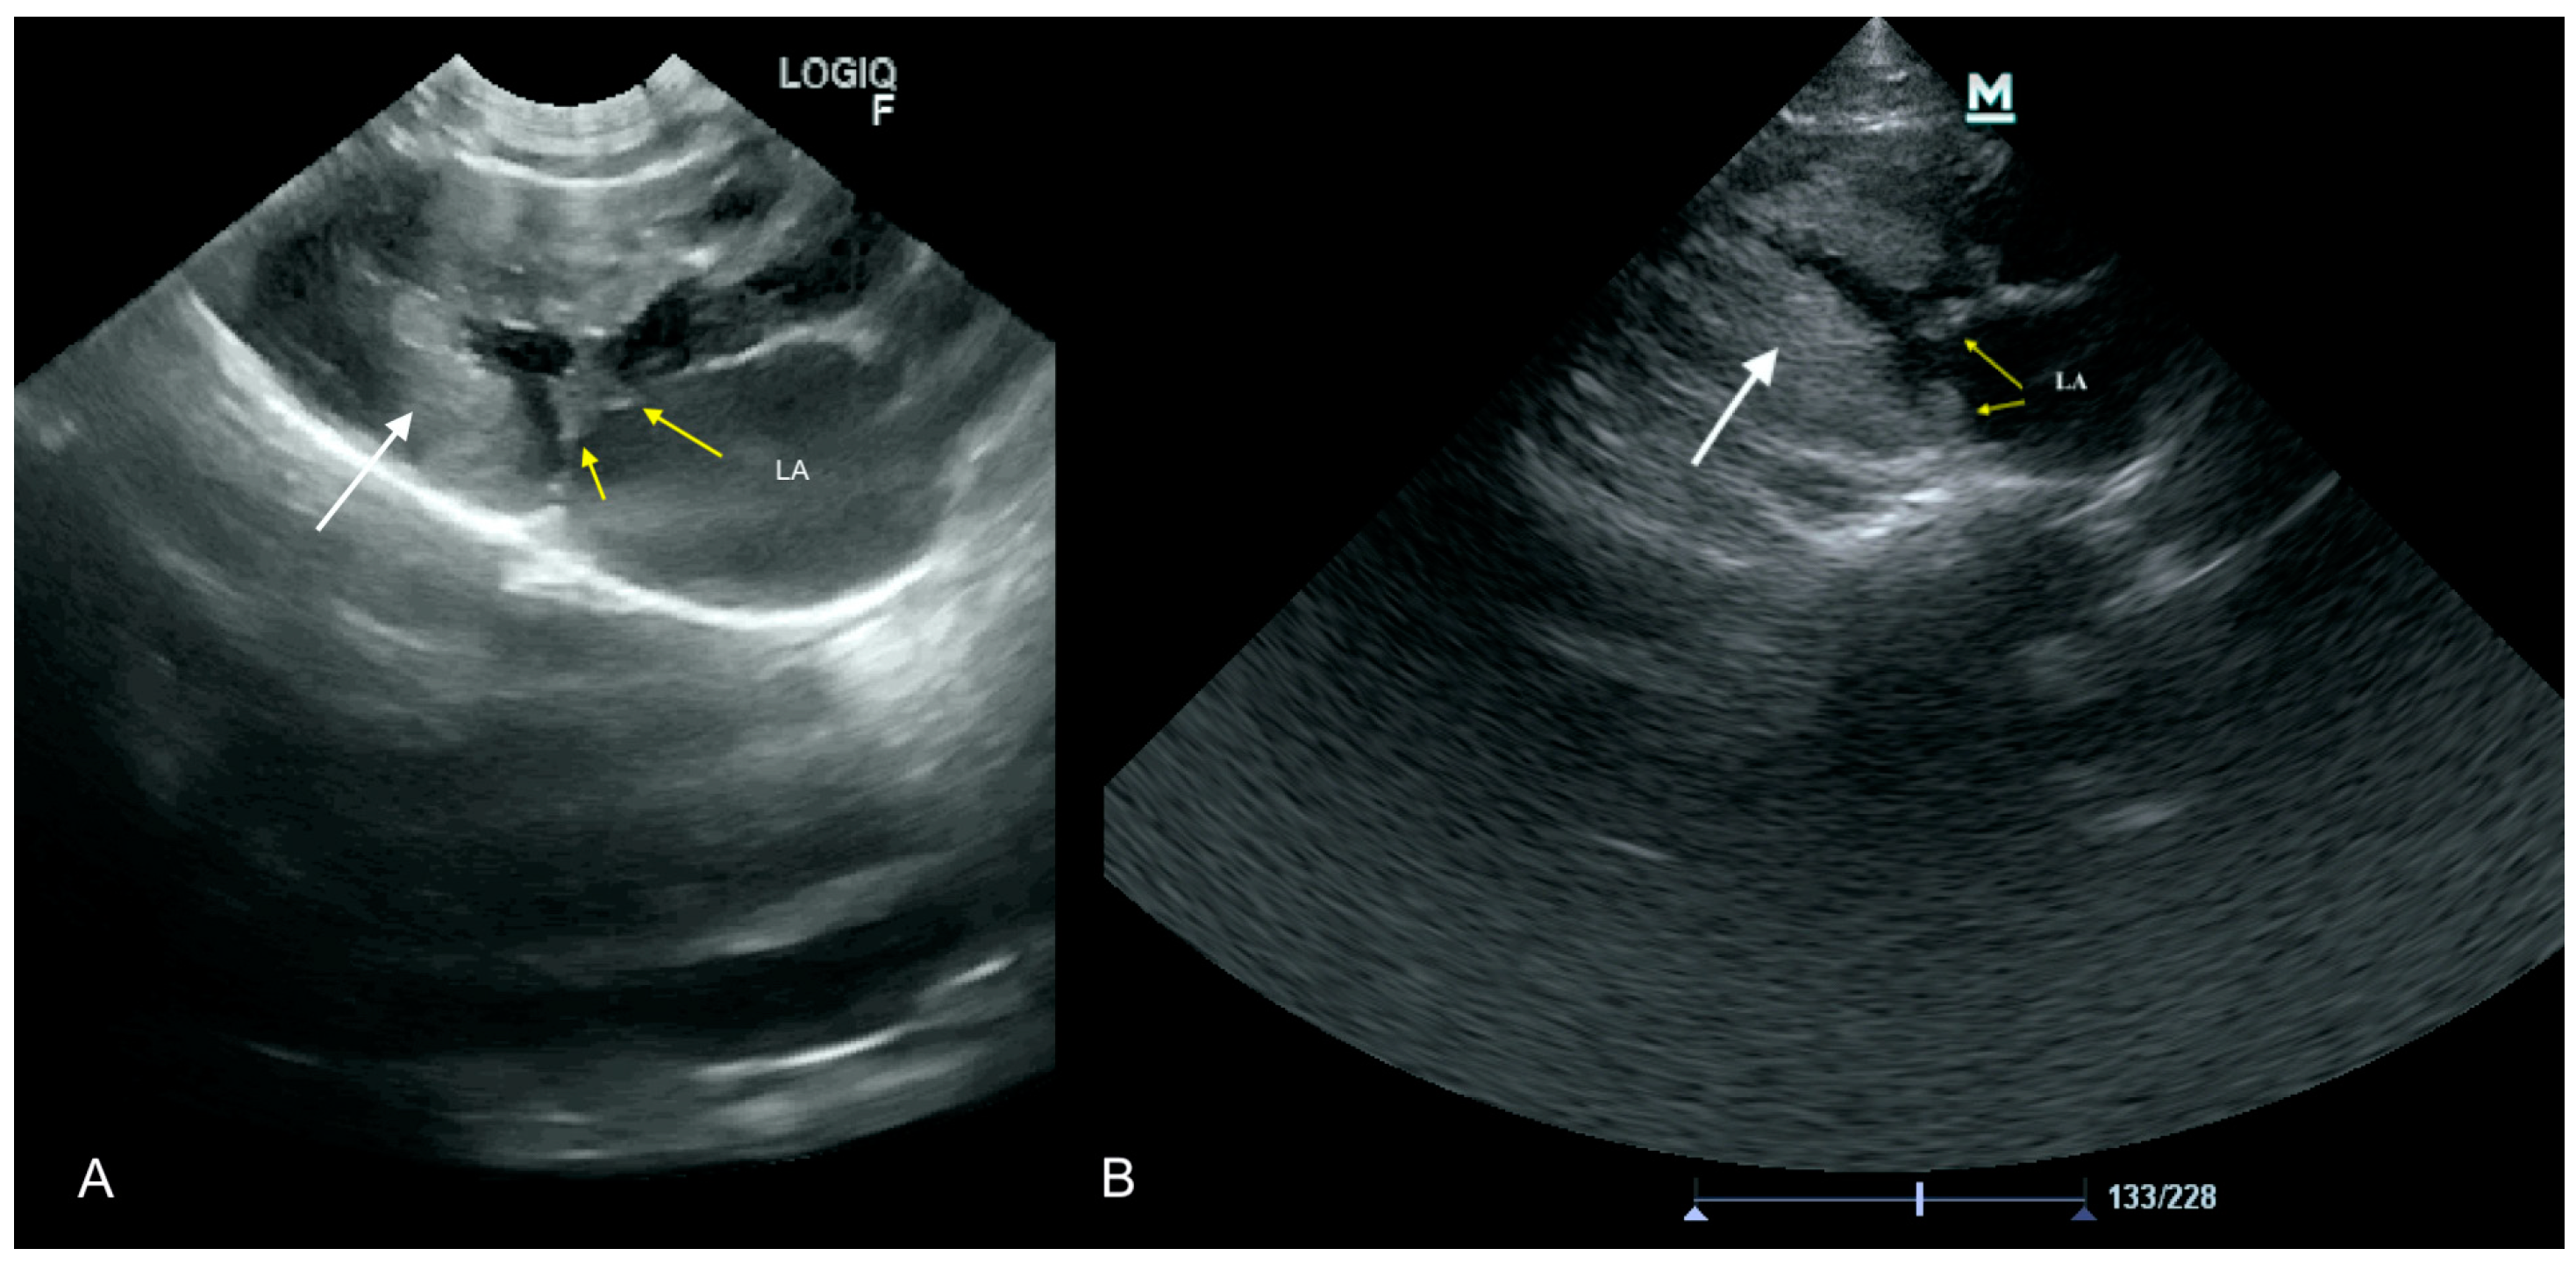

3.2. Case No. 2